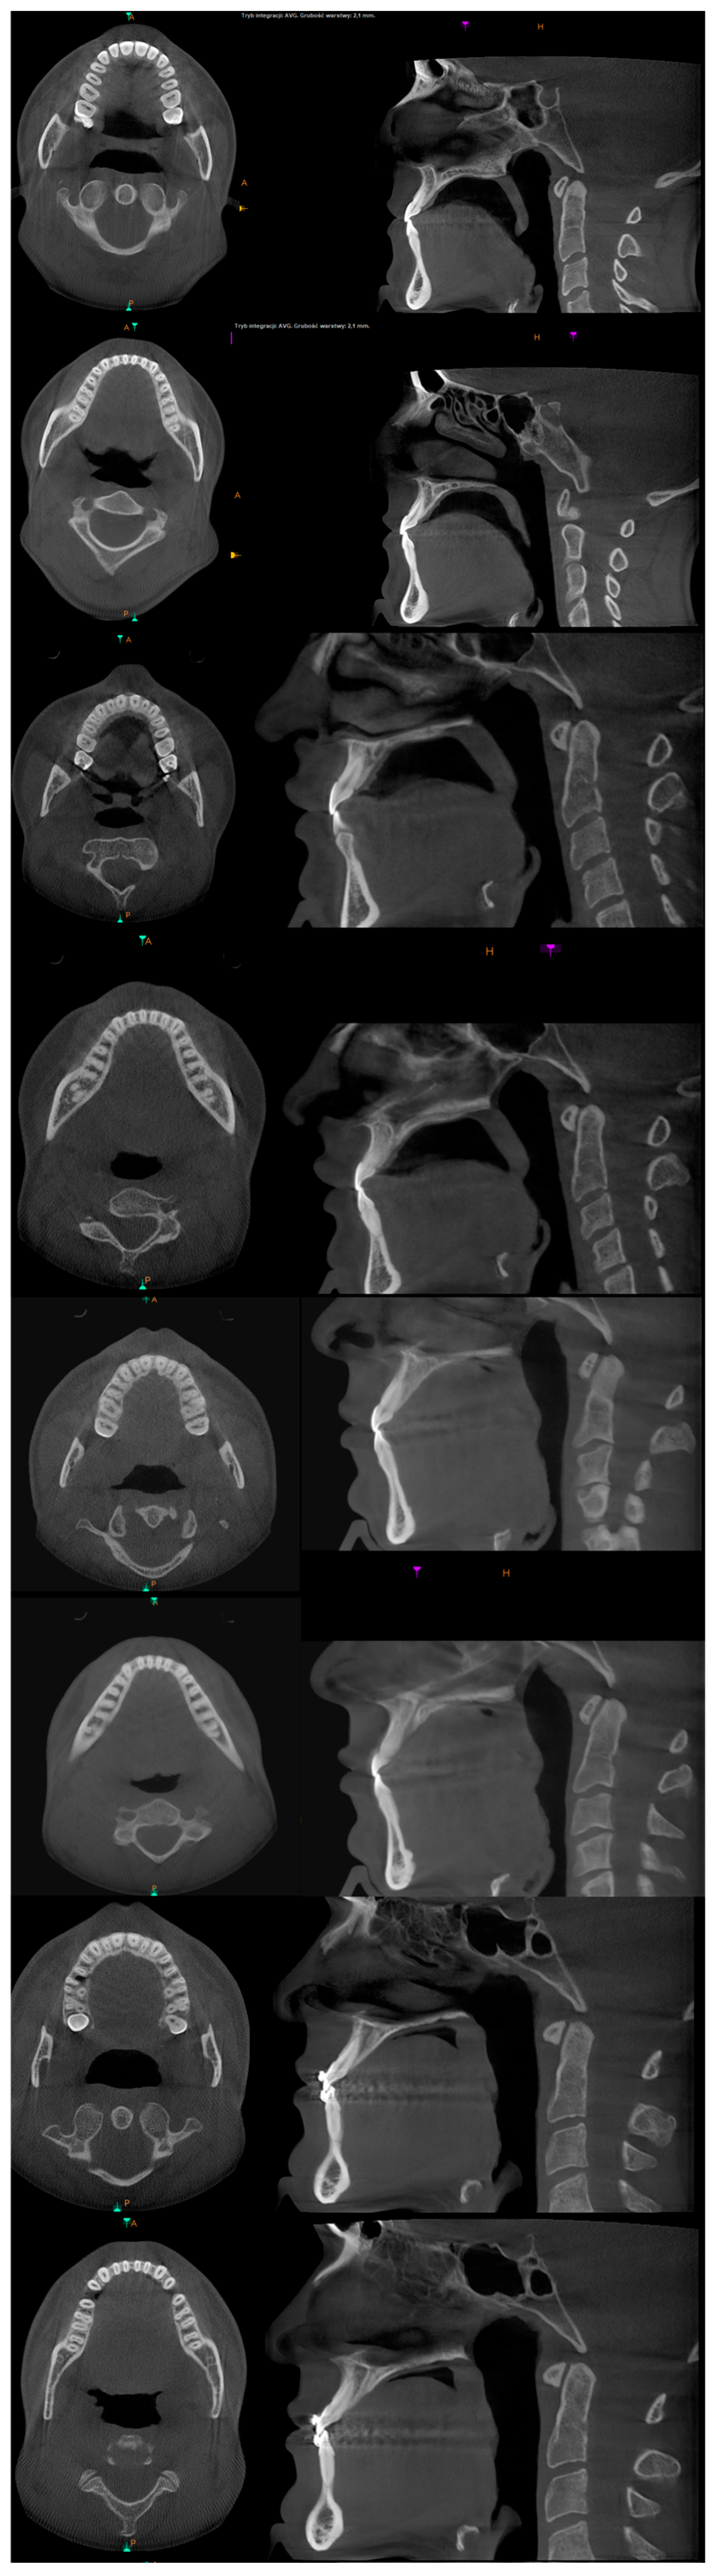

3. The Results of the Treatment